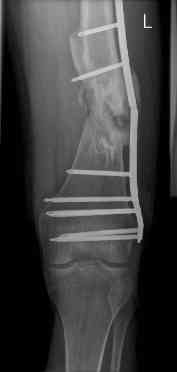

16 yr old boy, high energy motorcycle trauma trauma in July 2005 with:

- hip dislocation + acetabular fracture L

- distal femoral fracture L

- tibial shaft fracture L

- metatarsal fractures L

Sep 07

Nov 07

feb 07: retrograde nail + bone graft + BMP

may 07: dynamisation nail

sept 07: locking screw removal (max. dynamisation reached)

nov 07: persistant non-union distal femur; other fractures healed uneventfully.

All with gradual/partial weightbearing etc. Currently 50-100% weight bearing, no pain.

Soft tissues are intact. No smoking or diabetes. CRP <2

What would you do?